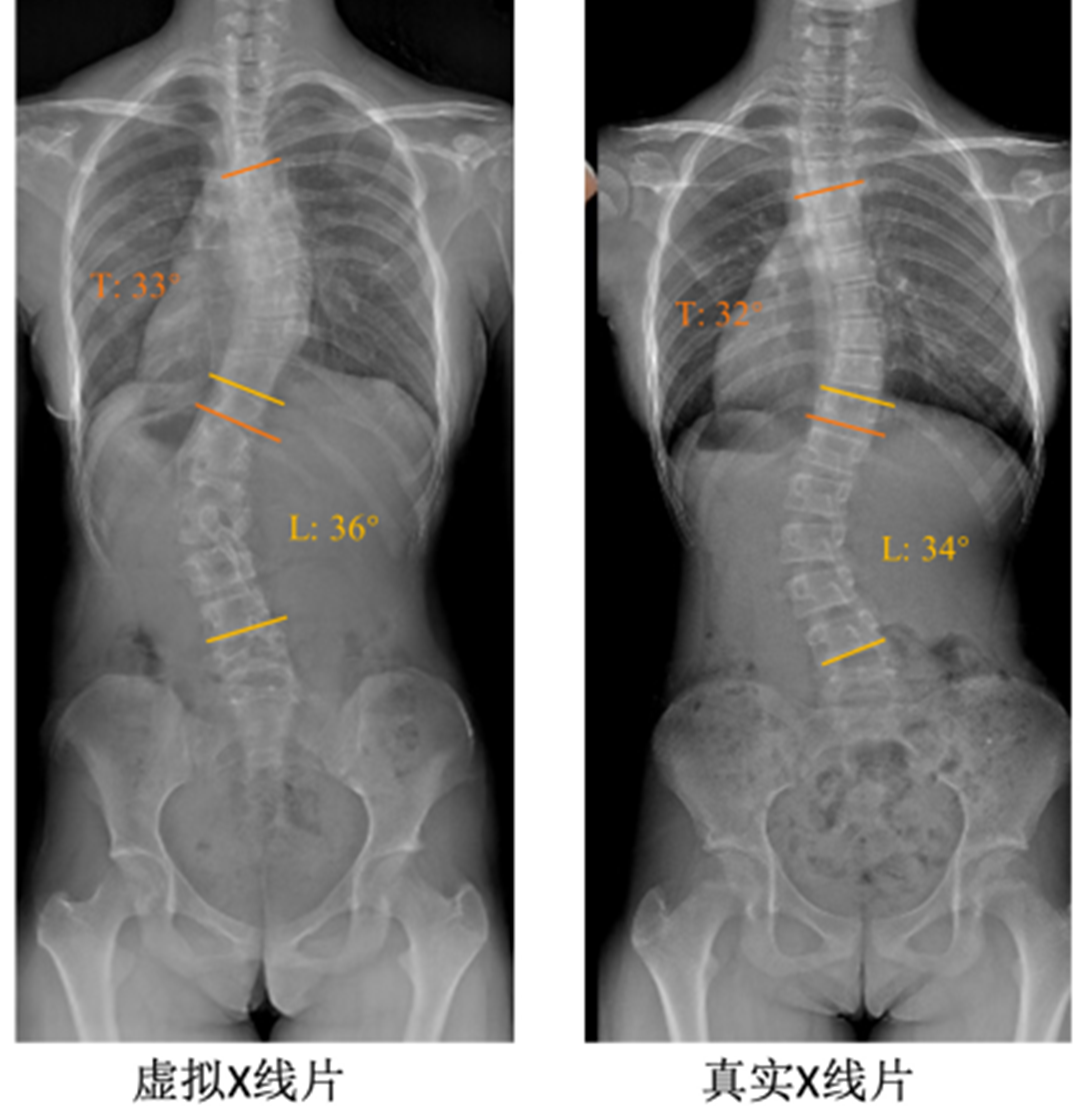

在南京鼓楼医院,11岁患者小月(化名)的妈妈给医生发来了一张手机拍摄的背部照片,并告诉医生她在孩子换衣服时发现孩子背后的蝴蝶骨不对称。照片通过手机端上传后,很快生成了一张虚拟的X线片,从而解开了疑问——脊柱侧凸。所幸发现得早,经过规律的支具治疗,配合康复训练,小月的脊柱侧凸有了明显改善,最终避免手术。